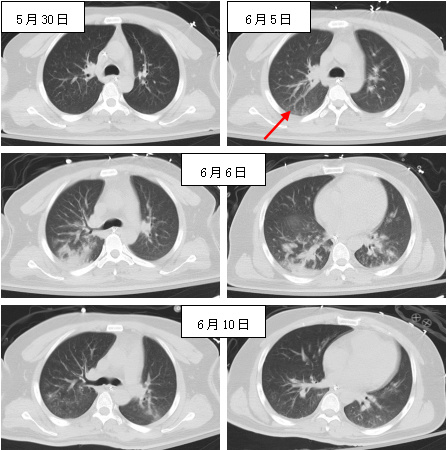

抗菌管理部门结合患者病史、检验检查结果以及微生物标本检验情况等研判,提出:(1)6月3日采集的4瓶血培养标本至6月7日仅1瓶报告检出CRKP,其他3份一直未生长,且之前连续数次血培养结果均为阴性,因此考虑该瓶阳性生长菌株为污染;(2)患者6月5日PCT最高达27.32 ng/mL,但6日早上未更改抗菌药物情况下已降至12.73 ng/mL,下降明显,提示美罗培南抗菌治疗有效,更不考虑CRKP血流感染;(3)该菌株可能是经导管采集血标本污染所致,污染源为呼吸道或皮肤定植的CRKP,因患者自5月27日起所送痰培养中即反复检出CRKP;(4)本次发热原因为新发吸入性肺炎,因5月27日、30日及6月1日肺CT均示已吸收(图 1),6月2日主管医生查房记录患者痰液增多,双肺湿啰音增多,6月5日复查肺CT右下肺有新发渗出,6日CT见右下背段及两下肺后基底段渗出范围扩大(图 2)。综合上述情况,拒绝使用多黏菌素的申请,令主管医生做好反流误吸的相关防控措施,并停用利奈唑胺,只需保留美罗培南(减量为1.0 g/8 h)。6月9日开始体温高峰下降,炎症指标继续降低(图 2),至6月14日神志进一步改善,体温已基本正常(最高37.6℃),转出ICU。

| 图 2 6月5日再次吸入性肺炎(箭头处),6日右肺下叶背段及两肺基底段渗出增加,6月10日基本吸收 |